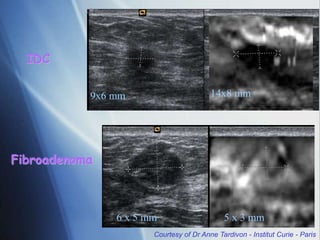

9x6 mm 14x8 mm

IDC

6 x 5 mm 5 x 3 mm

Fibroadenoma

Courtesy of Dr Anne Tardivon - Institut Curie - Paris